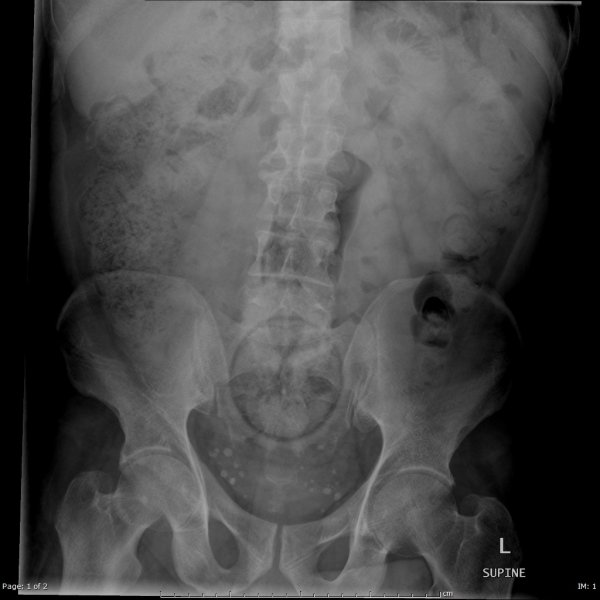

Специалисты по рентгеновской диагностике регулярно сталкиваются с посторонними предметами внутри тела человека. Обычно лишние предметы попадают в пищеварительную систему из-за неосторожности при еде или во время неудачных любовных игр. Почти всё удается вытащить — с хирургическим вмешательством или без него. выбрал самые необычные находки радиологов, которыми они делились на сайте Radiopaedia.org.